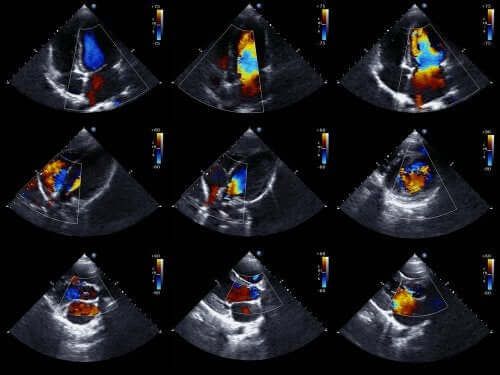

Echokardiogramy są jedną z najskuteczniejszych technik diagnozowania wrodzonych problemów z sercem. Oczywiście to także obejmuje wspólny pień tętniczy.

Lekarze zazwyczaj mogą zdiagnozować tego rodzaju anomalię jeszcze przed urodzeniem się dziecka. Aby to zrobić, używają do tego celu echokardiogramu płodowego. Jest to technika wykorzystująca fale dźwiękowe do odtworzenia ruchomego obrazu serca.

Korzystając z tej technologii możemy zobaczyć wygląd serca dziecka i zbadać jego funkcjonowanie, gdy jest ono jeszcze jeszcze w macicy. Dzięki tak uzyskanym informacjom lekarze mogą zaordynować właściwe leczenie natychmiast po urodzeniu dziecka.